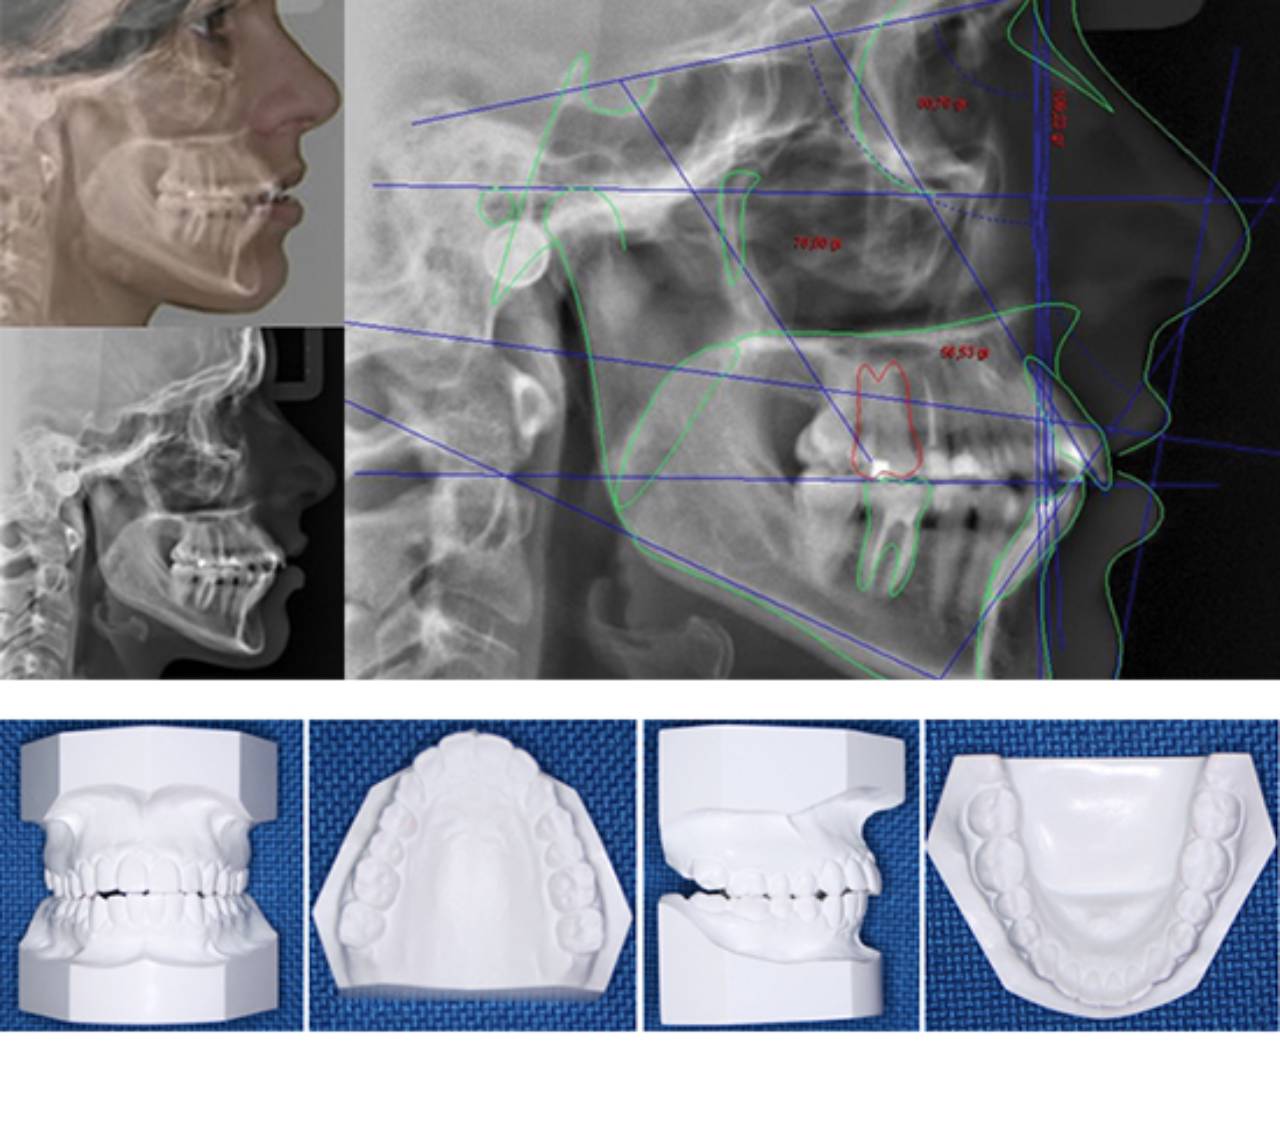

Documentação Ortodôntica

- Raio X Panoramico

- Raio X Periapical ( Incisivos suoerior e inferior)

- Telerradiografia com 2 análises cefalométricas

- Fotos intraorais

- Fotos Estraorais

- Modelo de Estudo